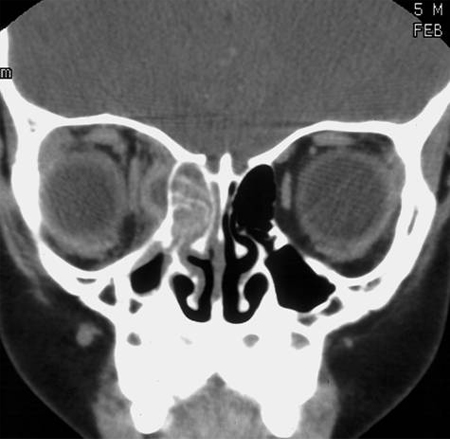

Edema periorbital ou malar, proptose orbital, perturbações visuais, movimentos extraoculares anormais ou sinais neurológicos anormais podem indicar a presença de complicações, sendo necessária uma consulta urgente de otorrinolaringologia.[Figure caption and citation for the preceding image starts]: Septo e corneto inferior direito visíveis antes da aplicação do descongestionanteDo acervo de Melissa Pynnonen, MD [Citation ends].

[Figure caption and citation for the preceding image starts]: Meato médio e corneto médio direito visíveis após a aplicação do descongestionanteDo acervo de Melissa Pynnonen, MD [Citation ends].